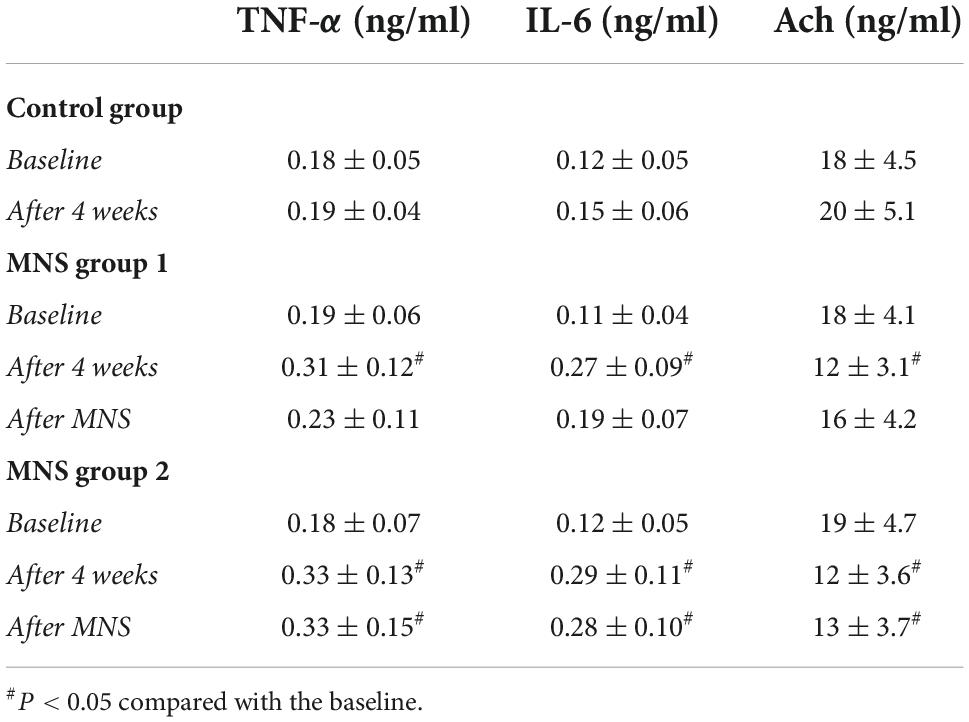

In both MNS groups 1 and 2, the blood concentrations of TNF-α and IL-6 were higher, whereas the level of Ach was lower after 4 weeks compared to the baseline condition. No significant difference was found in the TNF-α, IL-6, and Ach at baseline and after 30 min of MNS in the MNS group 1. However, the levels of the TNF-α and IL-6 were higher, while the level of Ach was lower after 30 min of MNS than baseline in the MNS group 2 (Table 3).

Table 3. Levels of the tumor necrosis factor-alpha (TNF-α), interleukin-6 (IL-6), and acetylcholine (Ach) in the plasma in control group, median nerve stimulation (MNS) group 1, and MNS group 2.

As highlighted in Table 4, the concentrations of TNF-α and IL-6 in the peri-infarct zone of LV tissues were significantly higher in the MNS group 1 (TNF-α: 0.21 ± 0.06 ng/mg vs. 0.13 ± 0.02 ng/mg, P = 0.02; IL-6: 0.16 ± 0.07 ng/mg vs. 0.08 ± 0.02 ng/mg, P = 0.03) and the MNS group 2 dogs (TNF-α: 0.30 ± 0.08 ng/mg vs. 0.13 ± 0.02 ng/mg, P < 0.01; IL-6: 0.26 ± 0.08 ng/mg vs. 0.08 ± 0.02 ng/mg, P < 0.01) than in the control group dogs. However, compared to the MNS group 2, the concentrations of TNF-α (0.21 ± 0.06 ng/mg vs. 0.30 ± 0.08 ng/mg, P = 0.04) and IL-6 (0.16 ± 0.07 ng/mg vs. 0.26 ± 0.08 ng/mg, P = 0.04) were lower in the MNS group 1 dogs, whereas the levels of Ach were higher in the MNS group 1 dogs than that in the control (18 ± 3.9 ng/mg vs. 12 ± 3.2 ng/mg, P = 0.02) and MNS group 2 dogs (18 ± 3.9 ng/mg vs. 10 ± 3.5 ng/mg, P < 0.01).

Table 4. Levels of the tumor necrosis factor-alpha (TNF-α), interleukin-6 (IL-6), and acetylcholine (Ach) in the left ventricular tissues in control group, median nerve stimulation (MNS) group 1, and MNS group 2.